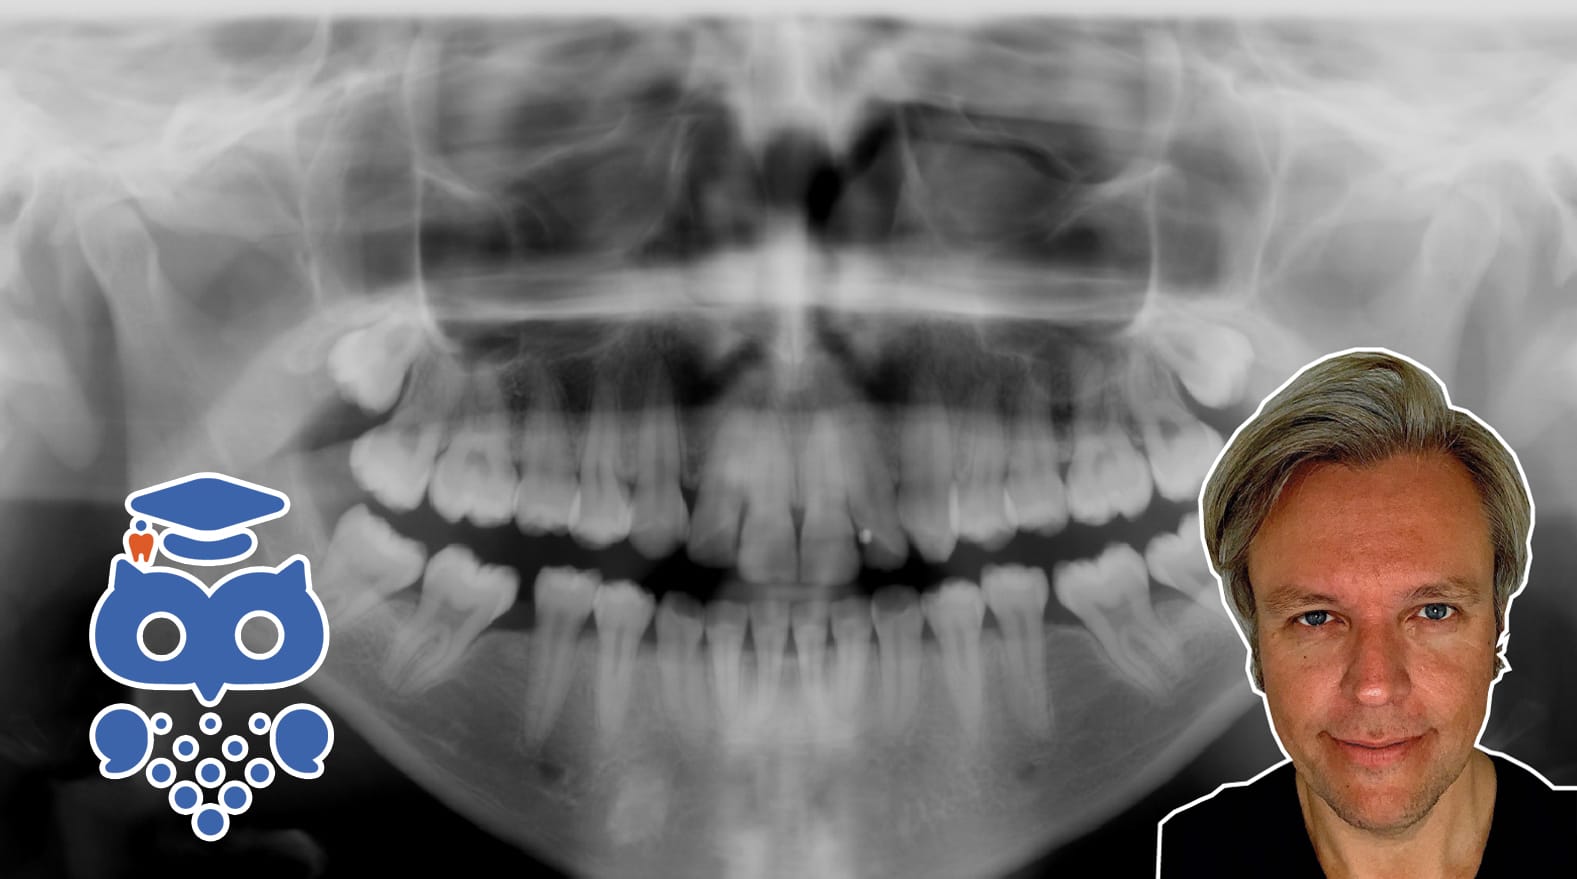

Panoramakörkort – panoramaröntgen, möjligheter och begränsningar

Se kursen på Tandakademin!